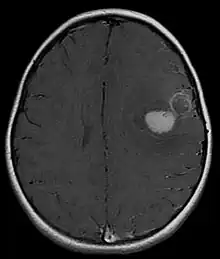

| Primitive neuroectodermal tumor of the central nervous system in a 5-year-old |

Several analysis can be used to determine the presence of the disease. Physical examinations showing papilledema, visual field defects, cranial nerves palsy, dysphasia, and focal neurological deficits are evidences for possible tumor.[2] PNETs can also be spotted through computed tomography (CT) and magnetic resonance imaging (MRI).[2] In images produced by MRIs, an irregular augmentation among a solid mass will indicated the presence of tumor.[3] However, the results of MRIs are usually ambiguous in defining the presence for this specific tumor.[2] In CT scans, the presence of PNETs will be indicated by an elevated density and an increase in volume of the brain.[2] The CT scan can also show calcification,[3] which is present in 41-44% of PNET cases.[2] Since the tumor can be replicated in other parts of the nervous system through the cerebrospinal fluid (CSF), a CSF analysis can also be conducted.[2] A spinal MRI is a fourth type of analysis that is useful in investigating the level of tumor propagation to the spinal cord.[2]